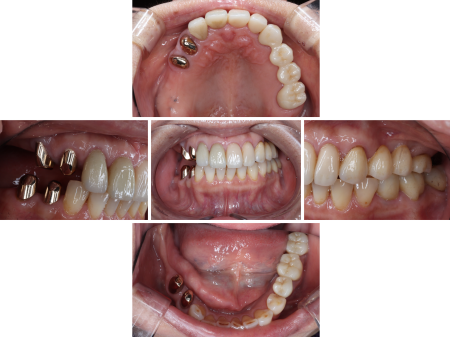

拝見したところ、上の奥歯6本(左第1小臼歯/4番、左右第2小臼歯/5番、右第1大臼歯/6番、左右第2大臼歯/7番)と右下の奥歯2本(第1大臼歯、第2大臼歯)が欠損しており、その部分を補うために装着されていた義歯が劣化している状態でした。

また、過去に一度、人工歯根をあごの骨に埋めて自分の歯のように噛める「インプラント治療」も検討されたとのことで、当院でも検査を行ったところ、やはりインプラントに必要な骨の量や高さが不足していました。

被せ物が装着されている歯のうち、左下の奥歯3本(第2小臼歯、第1大臼歯、第2大臼歯)と右上の前歯2本(中切歯/1番、側切歯/2番)は、過去に歯の神経が入っている管をきれいにして薬剤を詰める「根管治療」が行われており、右上の奥歯(第1小臼歯)と左上の前歯(犬歯/3番)、左上の奥歯(第1大臼歯)の3本は神経が残っていたものの、計6本については神経が炎症を起こしている状態でした。